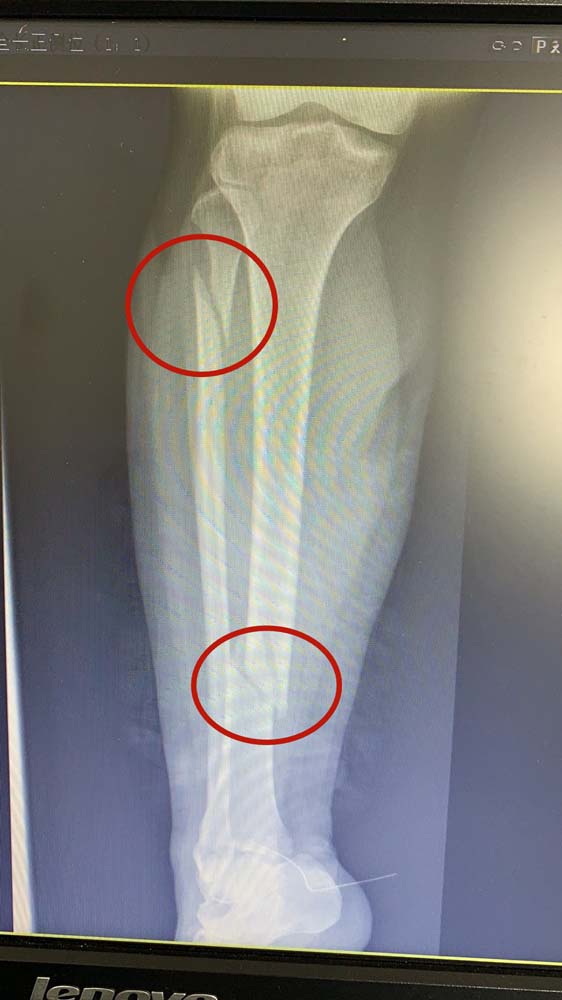

到达医院急诊后,化伟立即为张女士进行了X光片检查。果然,张女士右小腿下段胫骨骨折,右小腿上段腓骨骨折。吴飞华又披上白衣“战甲”,亲自操刀,为张女士进行急诊手术治疗,并收在医院8D病区住院治疗。

住院期间,8D病区医护团队为行动不便的张女士进行了悉心治疗和护理。好在张女士年纪轻,身体素质好,吴飞华为她进行了胫骨骨折闭合复位髓内针内固定术后,她的右腿经过一周时间的恢复和训练,已经达到了出院的标准。出院当天,张女士虽然坐在轮椅上,但还是连连向8D骨科的医生和护士们表示感谢。她说:“我这一跤虽然摔得重点,但是遇到了我的贵人——吴飞华医生和陶玲云护士,更遇到了一群好人——垂杨柳医院骨科的医生们和护士们。你们手术做得好,护理也做得好。有你们在,我这个本命年的坎啊,平安度过啦!”